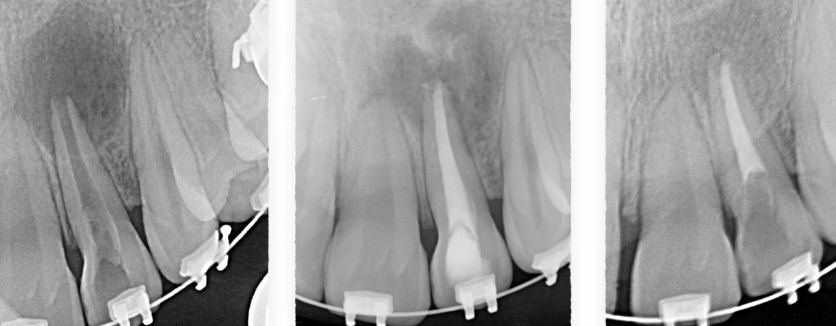

Fisuras

Los dientes fisurados muestran muchos tipos de síntomas, incluido el dolor al masticar, la sensibilidad a la temperatura o incluso la liberación de presión al morder. También es común que el dolor de dientes vaya y venga, lo que dificulta el diagnóstico de la causa del malestar.

La masticación puede causar el movimiento de las piezas fisuradas de su diente, y la pulpa dentro del diente se irrita. Al mismo tiempo, cuando se libera la presión de morder, la grieta puede cerrarse rápidamente, lo que produce un dolor agudo. Eventualmente, la pulpa se dañará y el diente dolerá constantemente, incluso cuando no esté masticando. Es posible que las grietas puedan provocar la infección del tejido pulpar, que puede extenderse al hueso y la encía que rodea el diente.

Diente fisurado tratable

Este tipo de fisura se extiende desde la superficie de masticación del diente y migra verticalmente hacia la raíz. En algunos casos, la grieta puede extenderse por debajo de la línea de las encías. Es posible que la grieta se extienda más hacia la raíz. El daño a la pulpa es común. En este caso, el tratamiento del conducto radicular suele ser necesario. Un diente roto que no se trata empeorará, lo que provocará la pérdida del diente. Por lo tanto, la detección temprana es esencial.